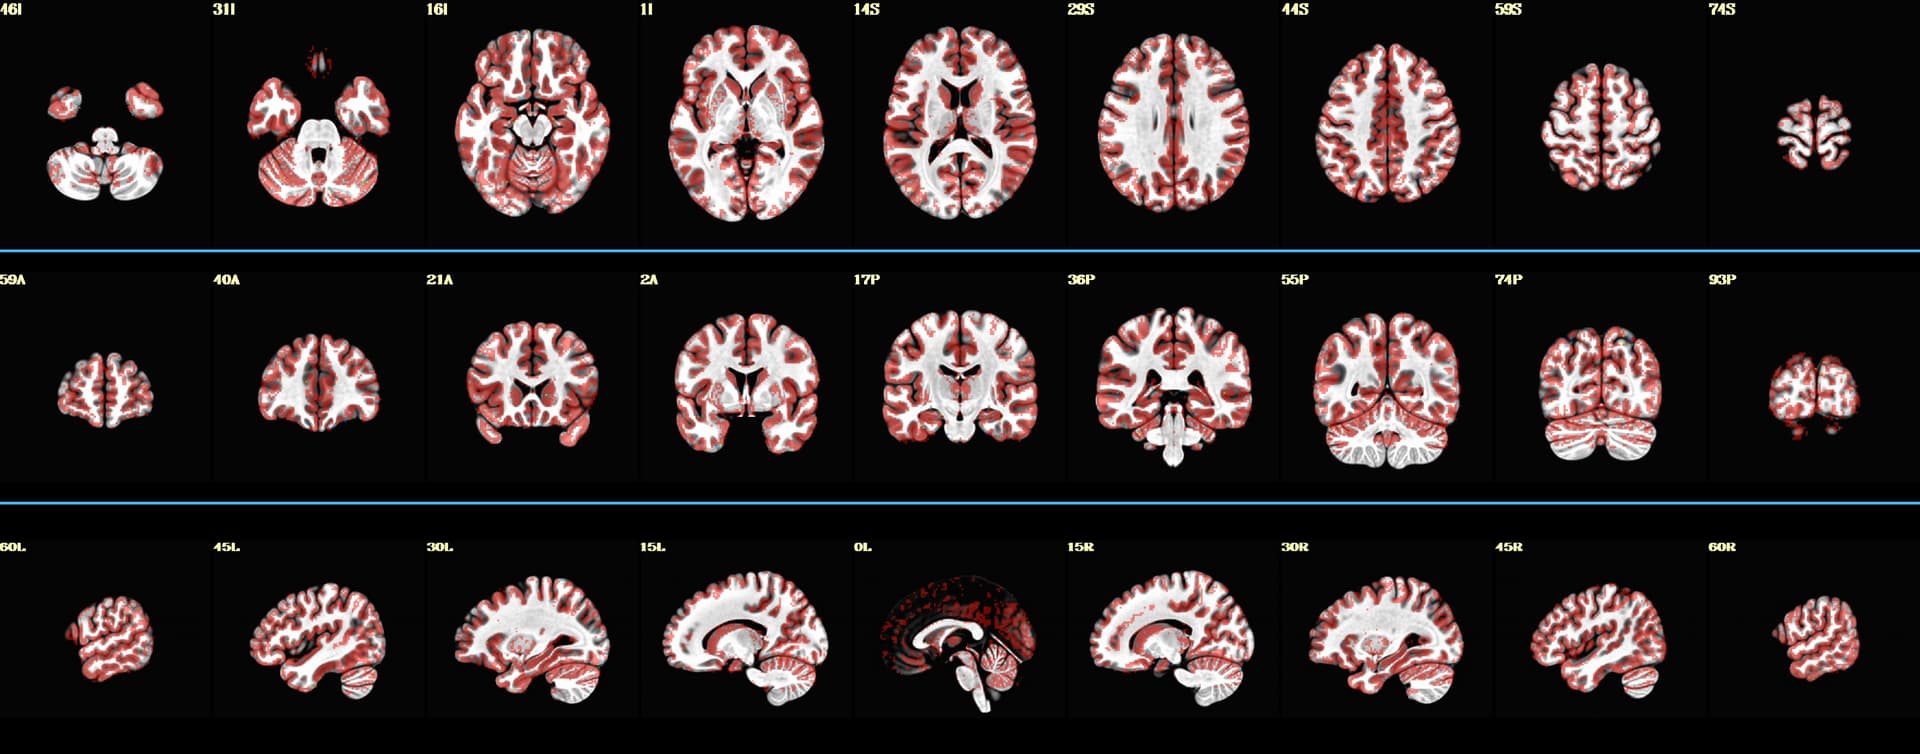

I would love to understand how can I script something to make images like such

I have found some new improvements by ptaylor, but I cannot find a reliable way to produce these images.

So far, code below can produce images like displayed below :